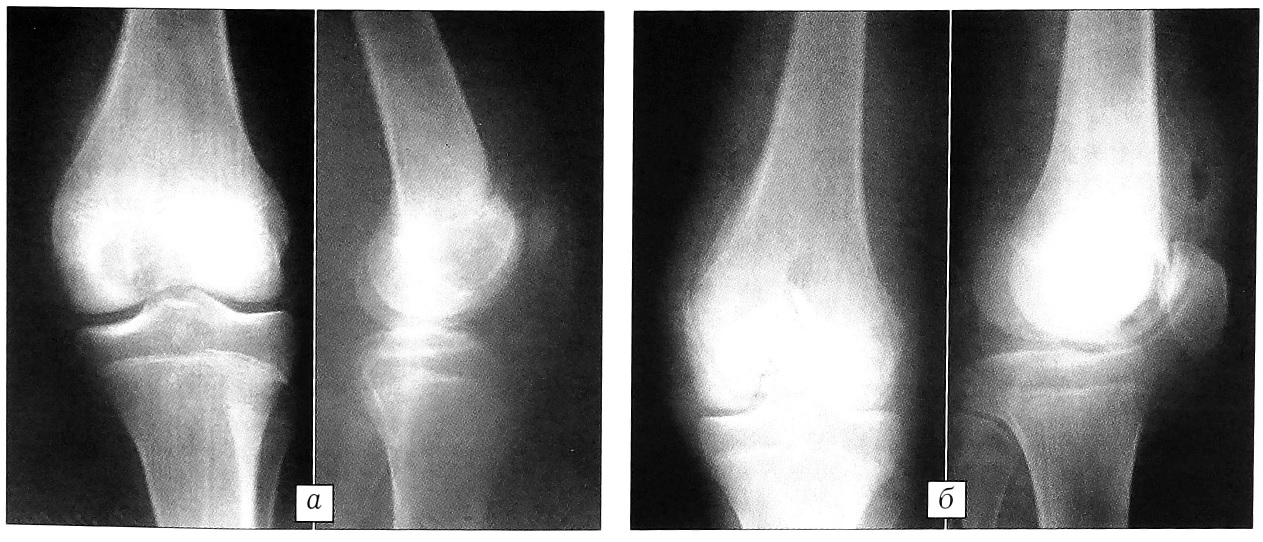

При небольших дефектах или дефектах неправильной формы «Перфоост» применяли в виде «костной щебенки» (стандартные пластины, расщепленные на более мелкие фрагменты) — чаще всего при пострезекционных дефектах эпифизов костей у больных с хондробластомами. Достаточная эластичность и механическая прочность «Перфооста» позволяли быстро и плотно заполнить дефект и создать прочную суставную поверхность (рис. 2).

Рис. 2. Рентгенограммы больного С. 15 лет. Диагноз: хондробластома дистального эпифиза левой бедренной кости. а — до операции; б — после субхондральной резекции дистального эпифиза бедра и аллопластики «Перфоостом» («костная щебенка»).